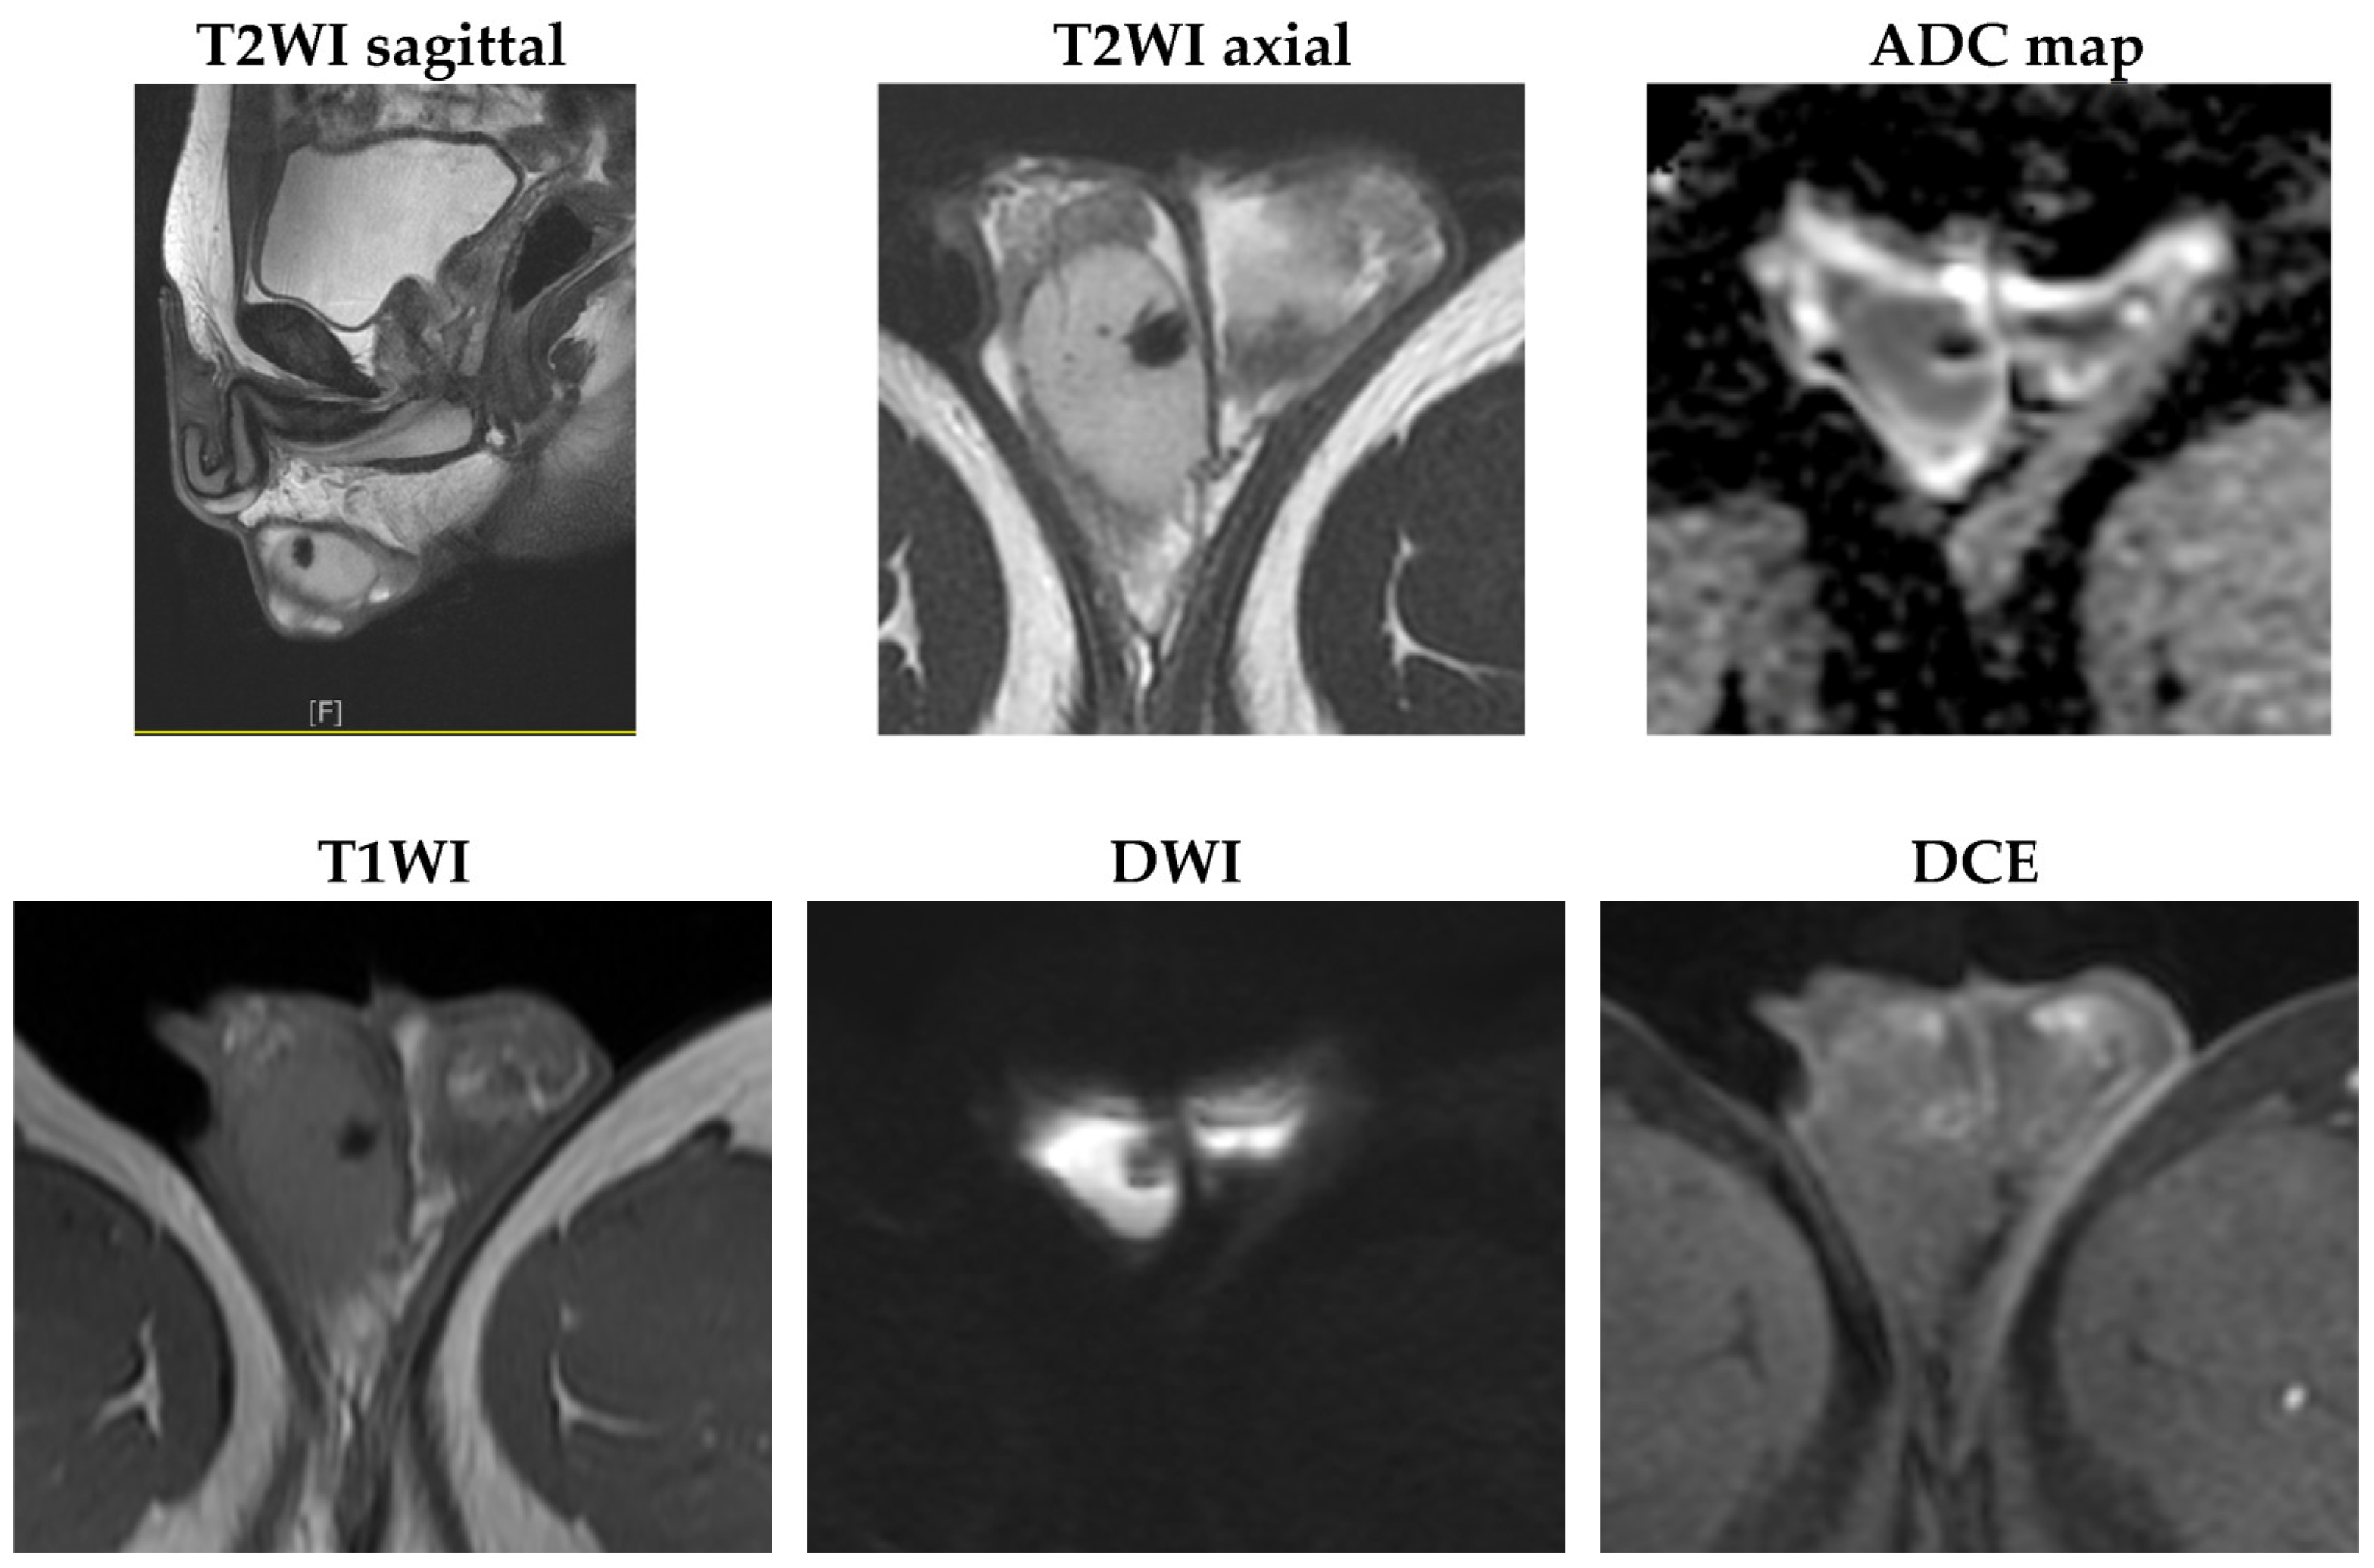

2. Case Presentation